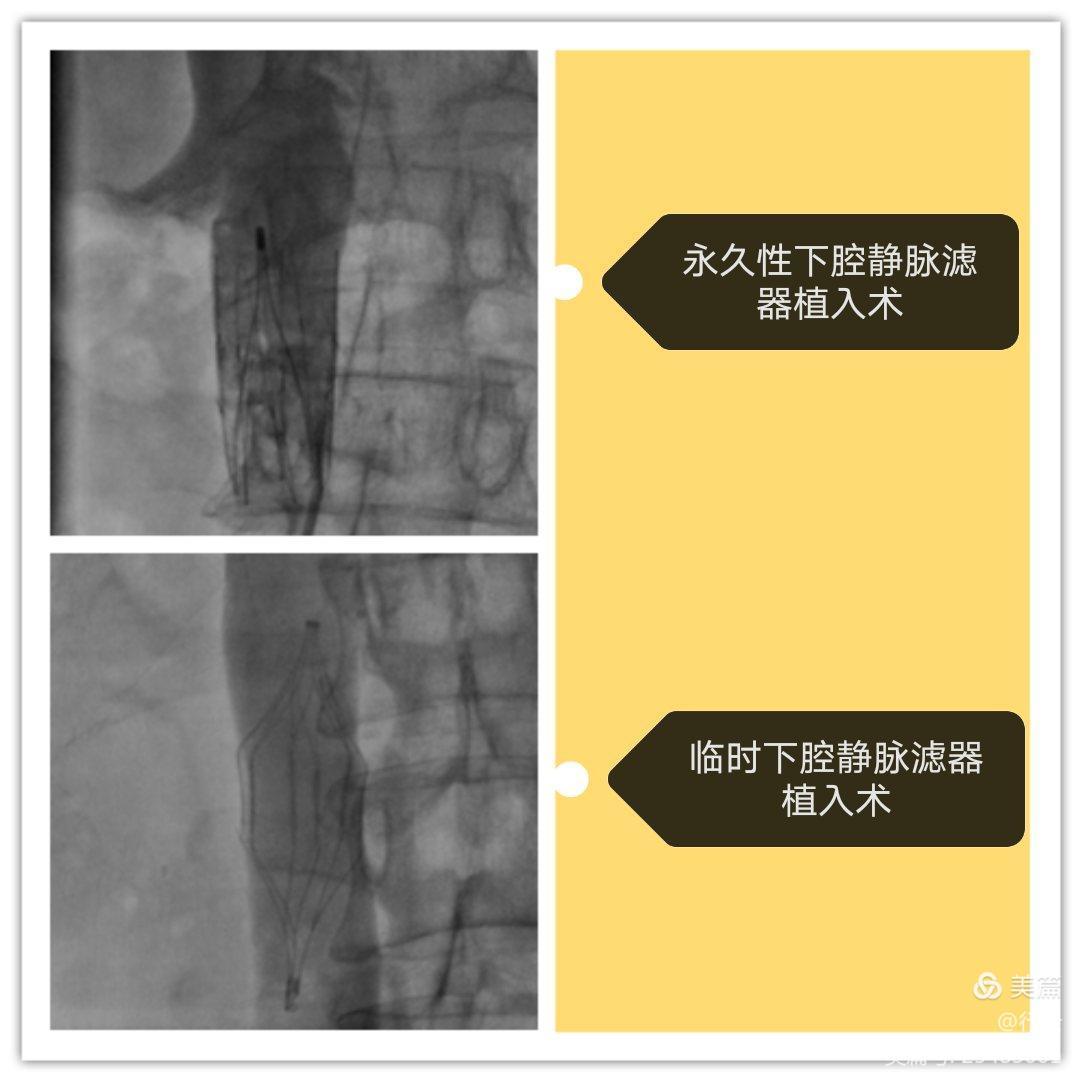

五、下腔静脉滤器植入术。